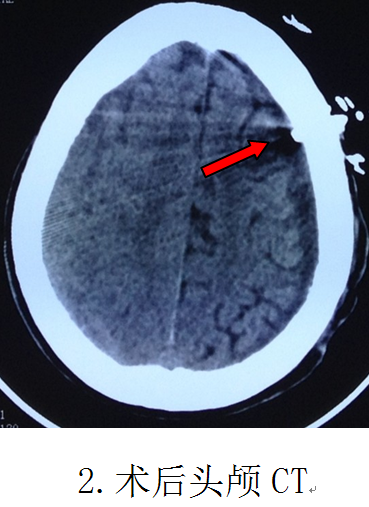

第二天即實(shí)施手術(shù),在局部麻醉清醒狀態(tài)下,順利實(shí)施了微創(chuàng)手術(shù)“雙管硬通道微創(chuàng)鉆孔沖洗引流術(shù)”,頭皮只有兩個(gè)0.3厘米直徑的點(diǎn)狀鉆孔穿刺損傷,術(shù)中沖洗出血腫100多毫升,整個(gè)手術(shù)時(shí)間僅需30分鐘。復(fù)查CT血腫完全清除,手術(shù)成功。當(dāng)天晚上病人精神明顯好轉(zhuǎn),偏癱的右手即能抬起來(lái)跟醫(yī)生握手。第5天下床行走,偏癱肢體完全康復(fù),取得立竿見(jiàn)影的效果。第8天順利出院。